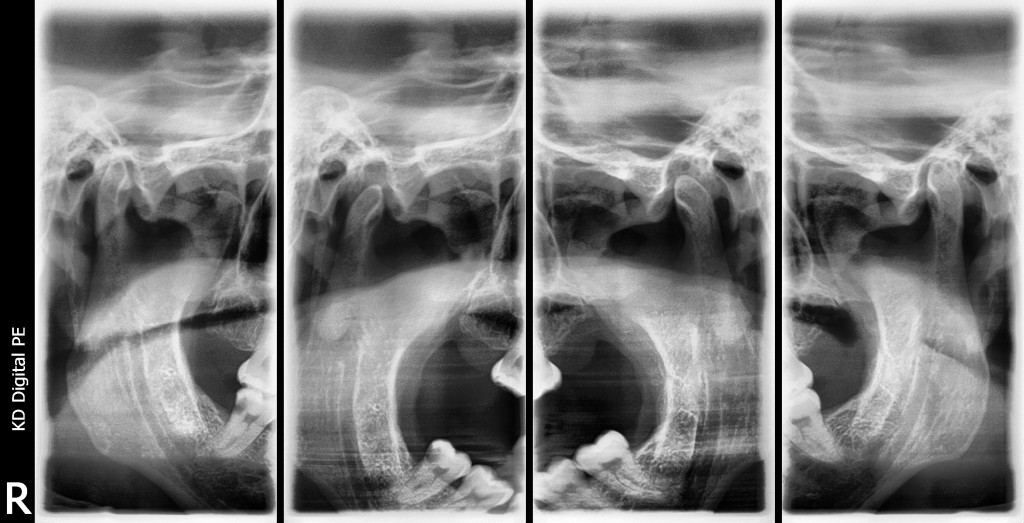

ATM

• Aumenta las posibilidades de analizar y realizar tratamientos eficaces en Patologías de la Articulación temporomandibular.